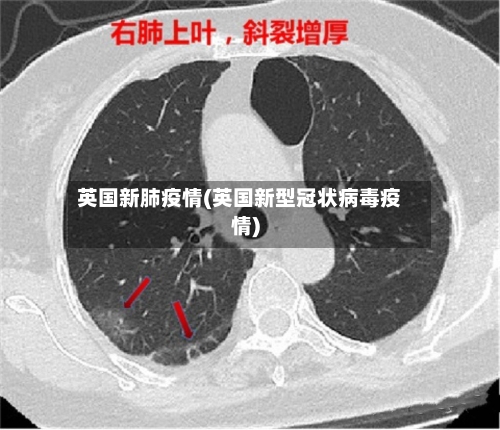

英国新肺疫情(英国新型冠状病毒疫情)

英国国家统计局的数据显示,英国各地感染新冠肺炎病毒的人数创历史新高。其中 ,70岁以上感染者比例达到6%,创下新的历史纪录 。据此前报道,英国国家统计局新冠肺炎疫情调查项目高级统计师卡拉表示 ,奥密克戎亚型突变株BA.2在英国各地的传播导致感染人数迅速增加。

英国:自2月宣布“与新冠共存”计划以来,新冠检测阳性者无需自我隔离,政府也不再追踪密切接触者,但疫情数据居高不下 。英国国家统计局(ONS)数据显示 ,英国大约每13人中就有1人确诊。奥密克戎BA.2毒株在英格兰地区快速传播,导致55岁以上群体感染率激增,比此前平均水平高出20倍。

英国。英国国家统计局的最新数据显示,英国大约每13人中就有1人确诊 。4月6日公布的研究结果还显示,奥密克戎BA2毒株正在英格兰地区快速传播 ,导致3月以来55岁以上群体感染率激增,比此前平均水平高出20倍。美国。随着奥密克戎BA2毒株的蔓延,全美新冠发病率再次上升 。